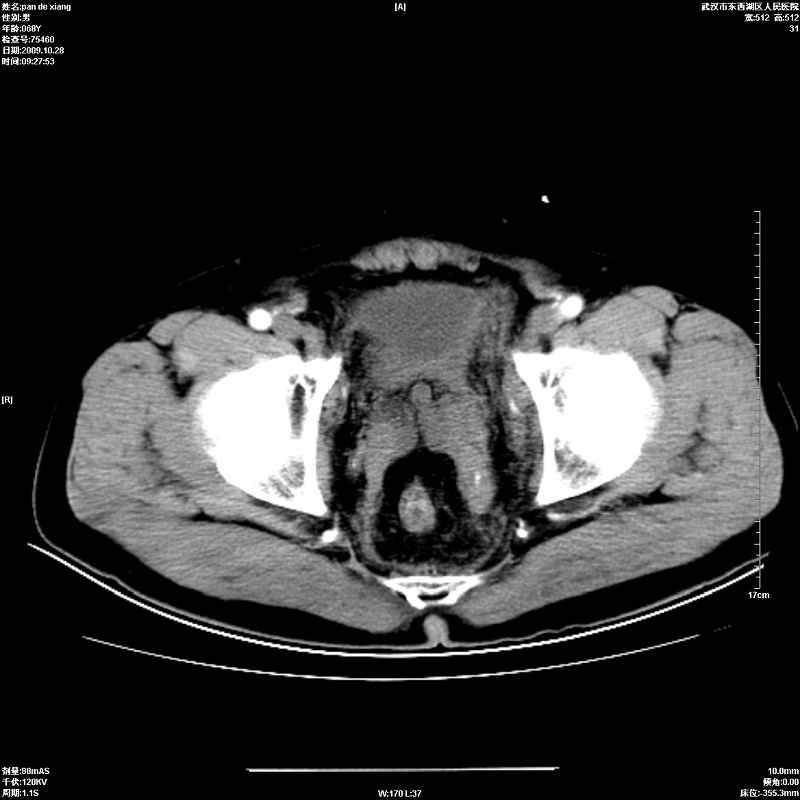

以下是引用杀毒软件在2009-10-28 20:41:00的发言:[br]结合临床考虑---白血病双肾改变或淋巴瘤。

以下是引用zxl51642在2009-10-29 9:59:00的发言:[br]结合临床“单克隆免疫球蛋白血症”,考虑双肾为继发损害并肾功能不全(尿中大量igg及少量iga、igm等大分子免疫球蛋白滤出所致继发损害),椎前软组织肿块为髓外造血。与浆细胞瘤有区别,平扫时有战友说的很清楚。